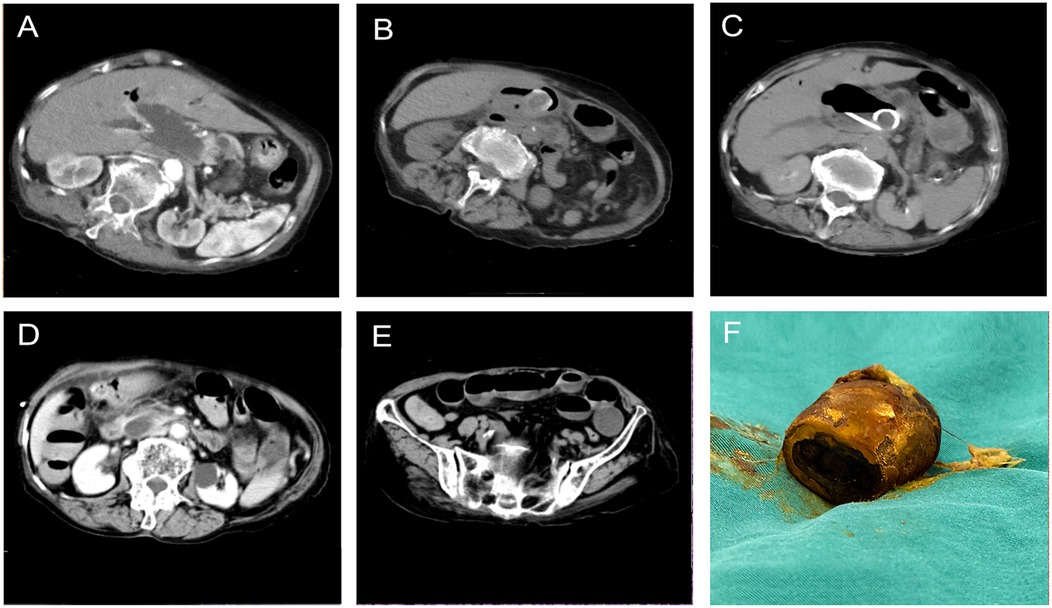

Background: Cholecystolithiasis is the most common disease of the gallbladder. Both acute obstructive suppurative cholangitis (AOSC) and gallstone ileus are critical clinical conditions requiring urgent intervention. However, their synchronous occurrence, particularly in elderly patients, presents a significant therapeutic challenge. In such scenarios, an optimal treatment strategy is essential to ensure patient safety while minimizing procedural risks. Case presentation: Herein, we described a 91-year-old women with cholecystolithiasis who was admitted for a day of abdominal pain accompanied by jaundice and fever. Upon admission, the patient was hemodynamically instable, and blood tests showed elevated white blood cell count and severe liver dysfunction. Emergency computed tomography (CT) revealed intra-and extra-hepatic bile duct dilation with pneumobilia, sludge-like stone at the distal common bile duct (CBD), a cholecystogastric fistula, and a gallstone within the gastric lumen. Soon after, the patient suffered from periumbilical pain. Re-evaluation CT showed the gastric gallstone had migrated into the intestinal lumen, causing gallstone ileus. We first performed ultrasound-guided percutaneous transhepatic cholangial drainage. Three days later, the symptoms resolved. We subsequently performed a curative surgery, including enterolithotomy, cholecystectomy, CBD exploration, and fistula closure. After surgery, the patient recovered successfully. At 3 months of follow-up, she resumed daily activities, with no adverse events. Conclusions: Synchronous AOSC and gallstone ileus can be life-threatening; however, AOSC carries a higher mortality risk and should be addressed as the immediate priority. In hemodynamically unstable patients, particularly the elderly, extensive surgery should be avoided in the acute phase to reduce perioperative risk. Once stabilized, enterolithotomy and definitive repair can be performed to achieve a favorable outcome.